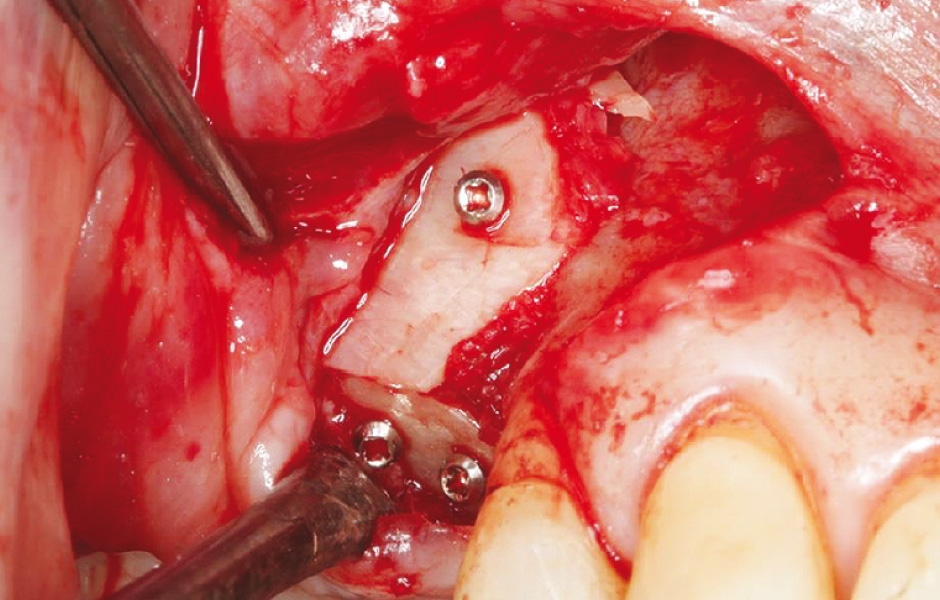

Obr. 2: Vytvoření kostního okénka mikropilkou včetně perforací pro fixaci resorbovatelnými stehy.

Obr. 5: Kostní víčko bylo znovu umístěno a původní implantáty odstraněny pro pokročilou periimplantitidu.